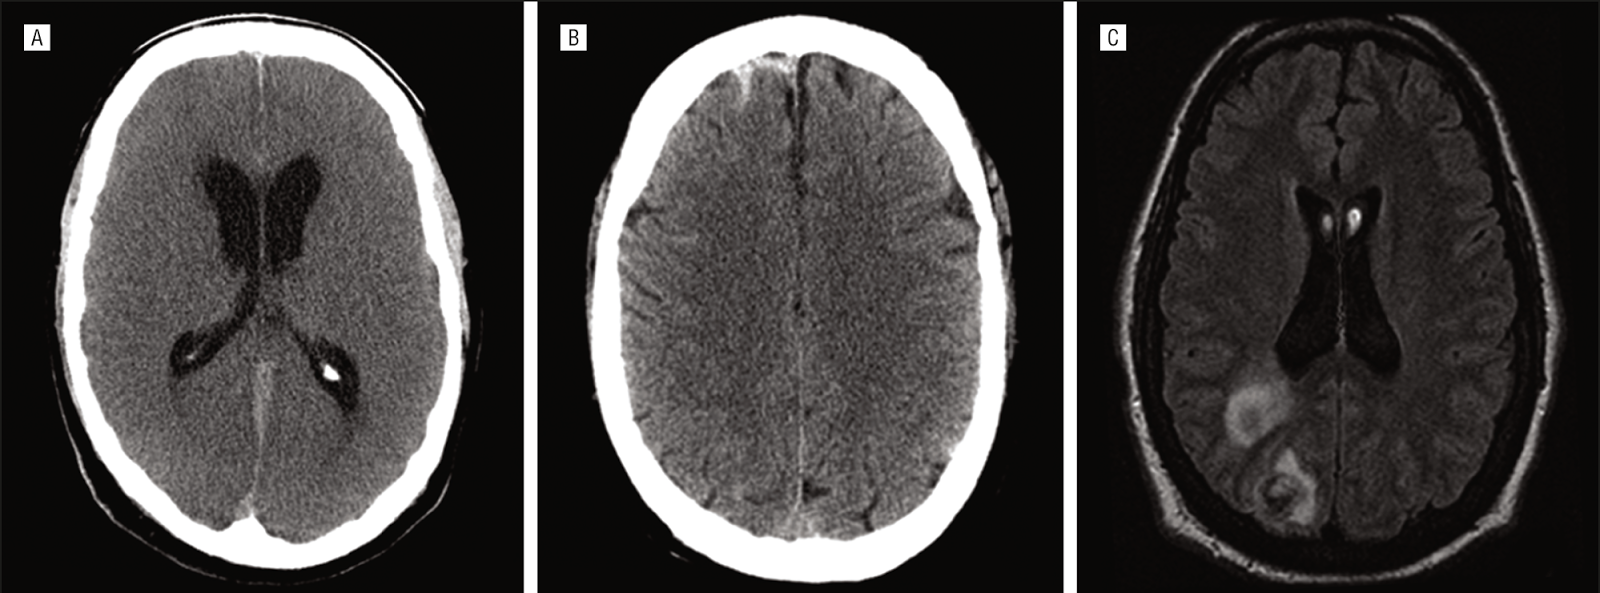

Modified from Fig. 4 (Mateen et al., 2011). Brain scans of adult patients who received extracorporeal membrane oxygenation (ECMO). (A) parafalcine subarachnoid hemorrhage and hydrocephalus on axial-view head CT, (B) diffuse subarachnoid hemorrhage on T1-weighted MRI, and (C) septic cerebral emboli on axial-view MRI.

Neurological events occurred in at least 50% (n=42) of patients treated with ECMO at one medical center over an 8 year period (Mateen et al., 2011). This is a conservative estimate, because a neurological exam was not performed in 21%, and over 70% did not have neuroimaging. Clinical presentation included new onset of coma and new loss of brainstem reflexes. Diffuse brain injury due to lack of oxygen (anoxia), global brain dysfuction (encephalopathy), subarachnoid hemorrhage (bleeds), and ischemic watershed infarction (stroke) were among the diagnoses. Of the 24 patients with brain scans, the findings were pathologically abnormal in 15 (see examples in figure above).